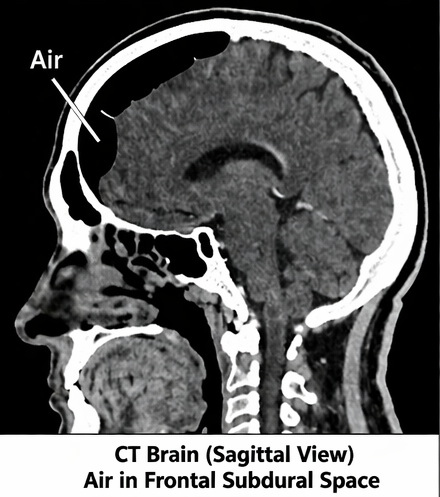

Computed Tomography (CT) Scan of Brain

Non-contrast CT scan revealed:

• Presence of air pockets in the frontal intracranial region

• Air accumulation in the subdural space

• Fracture of the frontal sinus

• No evidence of intracranial hemorrhage

A characteristic “Mount Fuji sign” was absent, suggesting non-tension pneumocephalus.

The frontal region is the most commonly affected site due to its proximity to paranasal sinuses. Fractures involving the frontal sinus or skull base create a pathway for air entry into the cranial cavity.

CT scan is the gold standard for diagnosis due to its high sensitivity in detecting even small volumes of air. The “Mount Fuji sign” is a classic radiological feature of tension pneumocephalus.